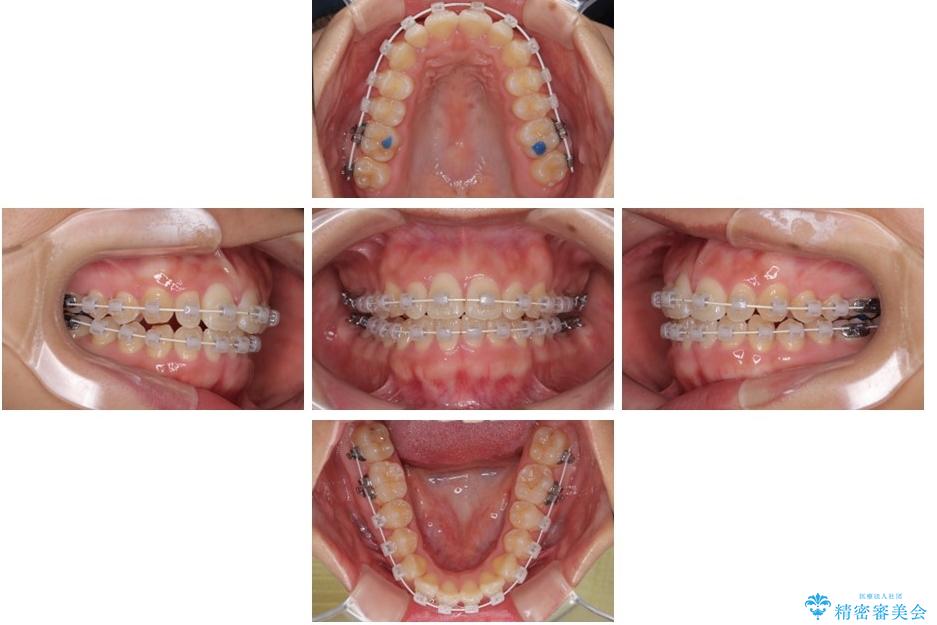

治療途中

• 目立ちにくい表側装置で1年完了!狭いアーチを側方拡大し前歯のデコボコを整えた症例 治療途中画像